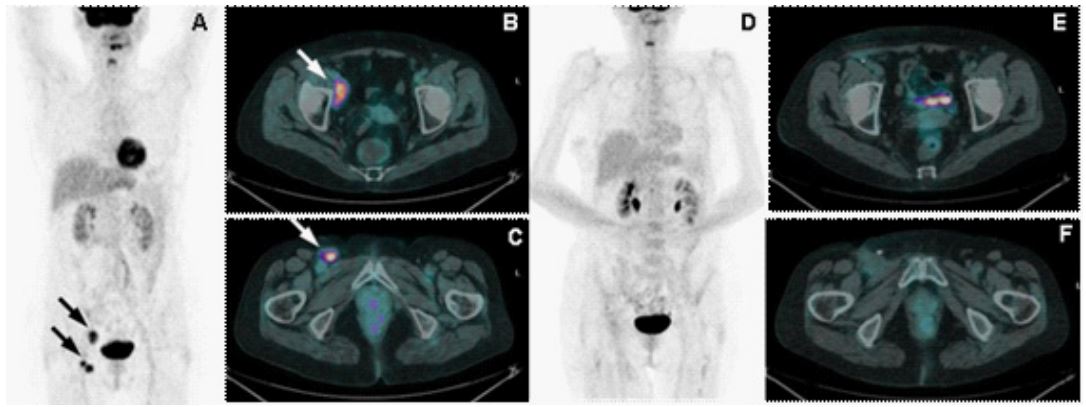

Figure 2: A: Maximum intensity projection image at diagnosis. B: high 8FDG uptake and enlargement of a right external iliac adenopathy. C: high 18FDG uptake and enlargement of a right inguinal adenopathy. D: Maximum intensity projection image after 3 cycles of chemotherapy. E: Non-uptake and non-enlargement of the previous right external iliac adenopathy. F: Nonuptake and non-enlargement of the previous right inguinal adenopathy

At our visit she was asymptomatic, presenting at the clinical examination palpable nodules in the right inguinal region. The Chest-Abdomen computerized tomography scan (CT-scan) showed a right external iliac (43 mm) and two inguinal lymph-nodes (20 mm). The somatostatin receptor scintigraphy (SRS) was negative, and the positron emission tomography with 2-deoxy-2-[fluorine-18] fluoro-D-glucose integrated with computed tomography (18F-FDG-PET/CT) showed high uptake in these lymph-adenopathies. (Figure 2. A, B and C).

Due to the quite extensive regional disease the European Institute of Oncology multidisciplinary team proposed systemic chemotherapy with carboplatin AUC 5 day 1 + etoposide 100 mg/m2 days 1-3 every 3 weeks. After three chemotherapy cycles, a radiological tumor response was observed (Figure 2. D, E and F). Therefore, in December 2009 a right iliac-inguinal lymphadenectomy was performed. The pathologist reported one out of seven adenopathies positive for MCC. An adjuvant radiotherapy was evaluated but excluded due to high risk of toxicity considering the severe post-surgical right lower limb oedema. Therefore, the multidisciplinary decision was to go ahead with chemotherapy completing six total cycles.